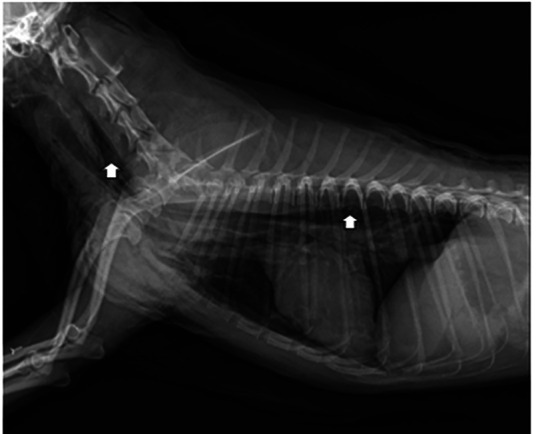

Materials and methods: A double-wire woven nitinol stent was handmade using a cross-and-hook knitting method. The fabricated endotracheal stent was 2-3 mm larger than the internal diameter of the ruptured trachea. The clinical signs and respiratory pattern, image diagnoses (radiography and computed tomography), and tracheoscopy results after endotracheal stenting were assessed for six months.

Results: The lateral cervical radiographs showed that the intratracheal stent was properly placed without migration or stent fracture at the insertion site. After two to three weeks of tracheal stenting, the coughing and dyspnea signs revolved, and the normal activities in all dogs were resumed.